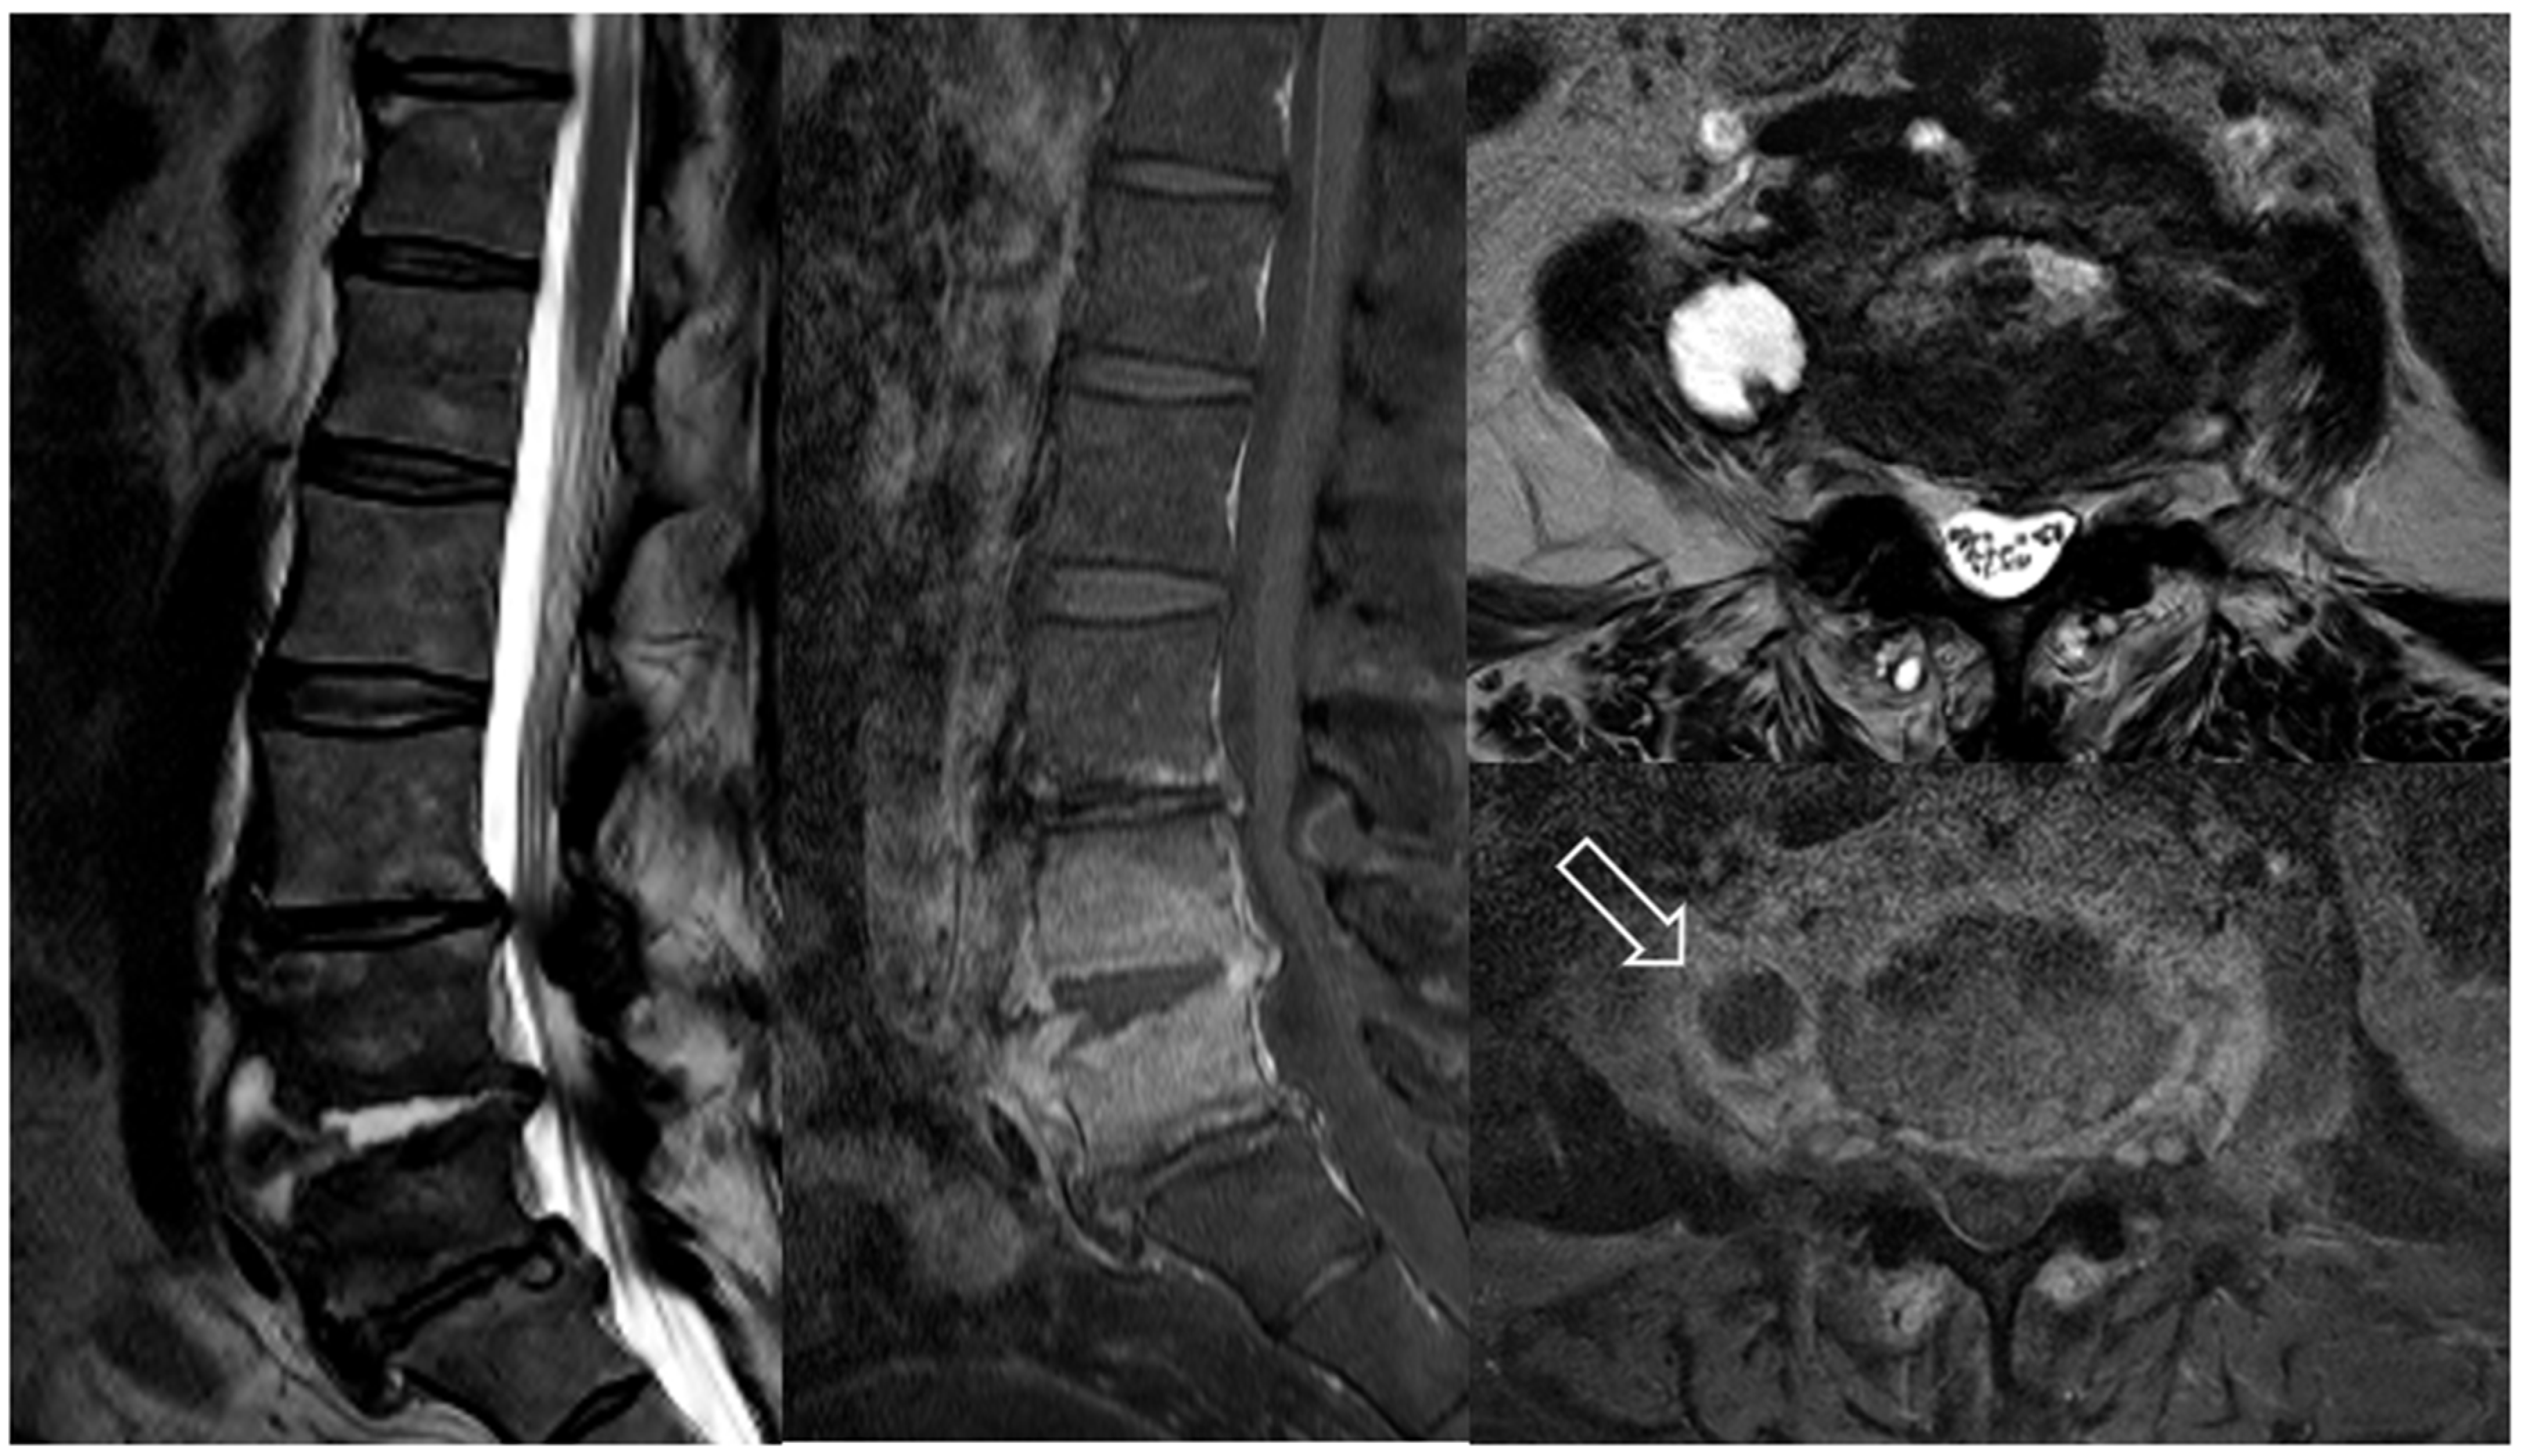

7.3. Imaging Tests

- Modic, M.T.; Feiglin, D.H.; Piraino, D.W.; Boumphrey, F.; Weinstein, M.A.; Duchesneau, P.M.; Rehm, S. Vertebral osteomyelitis: Assessment using MR. Radiology 1985, 157, 157–166. [Google Scholar] [CrossRef] [PubMed]

- Mavrogenis, A.F.; Megaloikonomos, P.D.; Igoumenou, V.G.; Panagopoulos, G.N.; Giannitsioti, E.; Papadopoulos, A.; Papagelopoulos, P.J. Spondylodiscitis revisited. EFORT Open Rev. 2017, 2, 447–461. [Google Scholar] [CrossRef]

- Sans, N.; Faruch, M.; Lapègue, F.; Ponsot, A.; Chiavassa, H.; Railhac, J.J. Infections of the spinal column—Spondylodiscitis. Diagn. Interv. Imaging 2012, 93, 520–529. [Google Scholar] [CrossRef] [PubMed]

- Sharif, H.S. Role of MR imaging in the management of spinal infections. AJR Am. J. Roentgenol. 1992, 158, 1333–1345. [Google Scholar] [CrossRef]

- Stäbler, A.; Reiser, M.F. Imaging Of Spinal Infection. Radiol. Clin. 2001, 39, 115–135. [Google Scholar] [CrossRef]